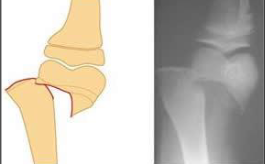

What type of fracture is this?

Epiphyseal fracture

more common in younger age